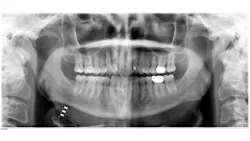

As a dental hygienist, if you saw this panoramic image, what would you think?

One afternoon in private practice, I took a panoramic radiograph like any other day. When evaluating the radiograph, I noticed a radiolucent wiring that confused me. I didn’t remember my patient having a history of any oral surgeries that would indicate this.

The patient informed me that the wire I was seeing was a new device to treat his sleep apnea. The patient then asked if I had ever heard of Inspire. I said no and felt humbled. As a dental hygiene educator, I like to think I am up-to-date on the latest oral health news, but this new device for the treatment of sleep apnea was news to me! I hope I can educate my fellow oral health colleagues on this device and how it could be a life-changing solution for those with moderate to severe sleep apnea.

I hope you have found this information to be beneficial. If nothing else, you won’t be caught off guard by those strange wires the next time you take a panoramic on a patient who has the Inspire device.